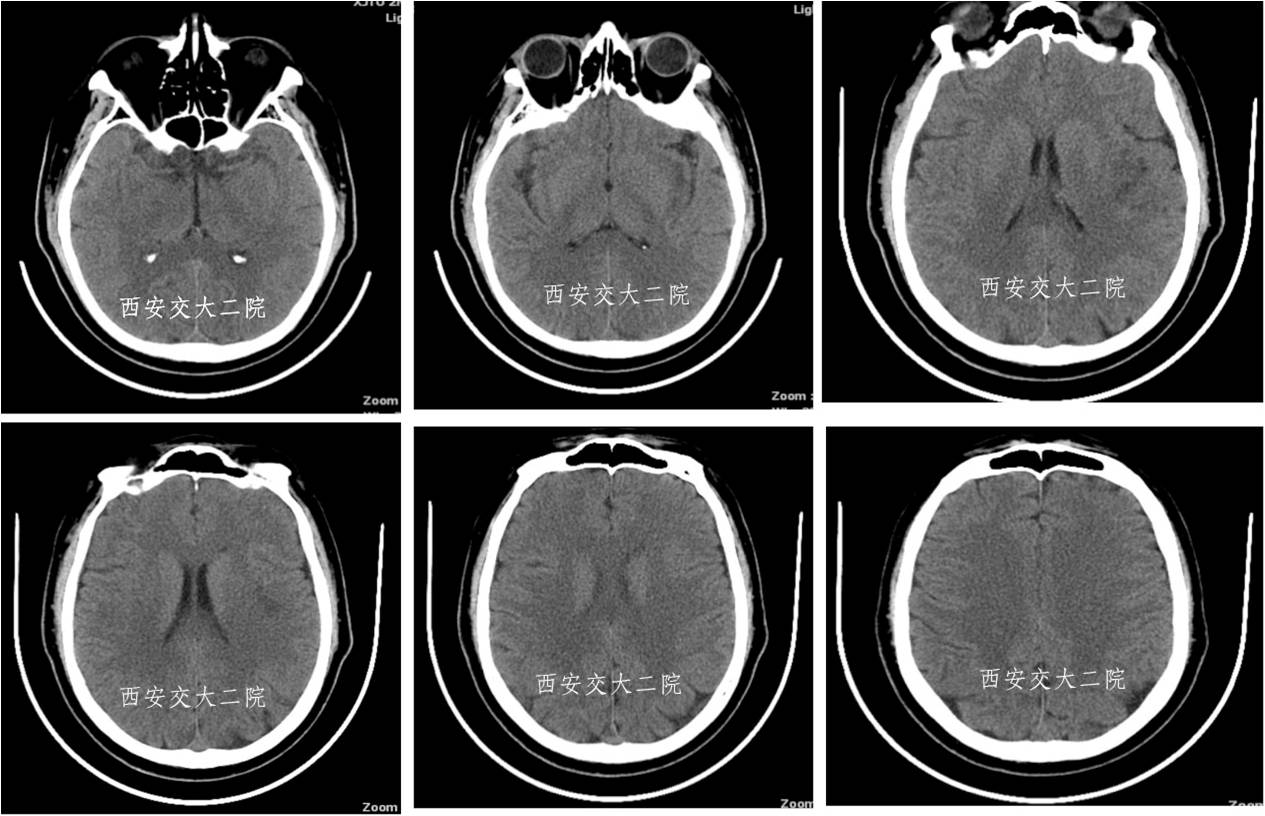

Case 4 颈内动脉颅内段闭塞再通术

》女,57岁;

》左侧肢体无力1月于2014.1.8入院;

》诊断:脑梗死(右侧半卵圆中心)。

术前脑CT

术后患者病情逐渐好转。

术后3月自动停药,1年后再发右侧颈内动脉供血区脑梗,复查DSA见再通支架处血管再次闭塞。